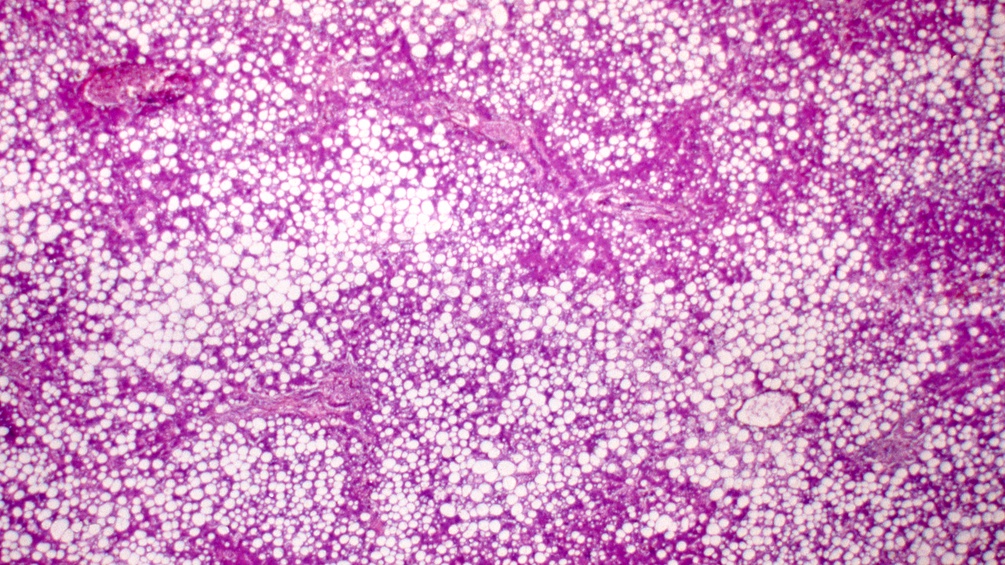

Unsere Leber hat, als zentrales Stoffwechselzentrum des Körpers, eine Menge zu stemmen. Nicht nur Alkohol oder Medikamente, sondern auch eine ungesunde Ernährung können das Organ rasch mal an seine Grenzen bringen. Es kommt zu einer Einlagerung von Fett in den Leberzellen und damit zu einer Vergrößerung; die Leber wächst demnach mit ihren Aufgaben (O-Ton: Eckart von Hirschhausen, deutscher Arzt und Kabarettist). Die Fettleber (Steatosis hepatis) gilt als erste Stufe eines krankhaften Umbaus und verläuft oft symptomlos. Bei jeder fünften erwachsenen Person lässt sich hierzulande im Ultraschall eine derartige metabolische Fettleber (MASLD, metabolically associated steatotic liver disease) diagnostizieren. Eine Volkskrankheit also, die den Leberexpertinnen und -experten Sorge bereitet, gilt sie doch als Vorläufer für eine Leberentzündung (MASH), eine Zirrhose oder Leberkrebs.